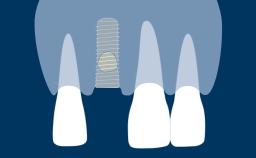

O tratamento com implantes dentais requer um procedimento cirúrgico para a instalação do implante e muitas vezes envolve procedimentos cirúrgicos adicionais, como extração dentária e aumento ósseo. Cada procedimento cria uma ferida. Para uma cicatrização ideal, os retalhos cirúrgicos - e muitas vezes outras feridas cirúrgicas - devem ser adequadamente fechados com suturas. O fechamento satisfatório de feridas e retalhos cirúrgicos promove a cicatrização e reduz complicações como abertura da ferida, deiscência e infecção. Este módulo apresentará os materiais e as técnicas apropriadas para sutura que contribuem para um resultado bem-sucedido, bem como técnicas inadequadas que podem levar a possíveis complicações.